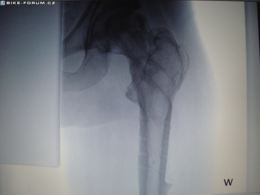

Poúrazová nekróza...